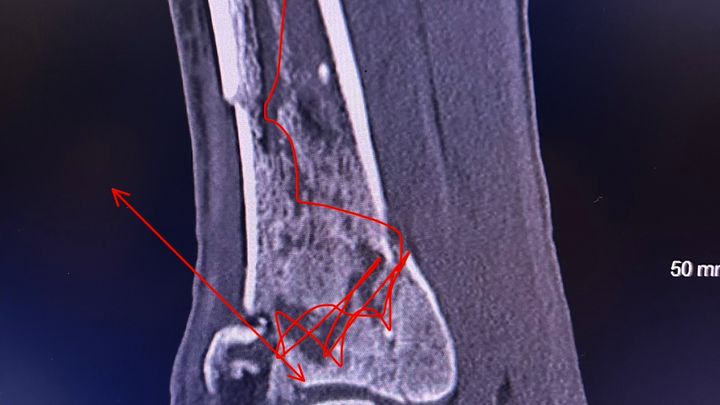

On January 22nd at 10:49 AM, I got the call no one ever wants to receive. It was John, screaming that he had fallen. In that moment, everything stopped. John fell approximately 20–25 feet, causing severe injuries from his left knee down. We are incredibly grateful and beyond blessed that he is alive today, because this situation could have ended very differently.